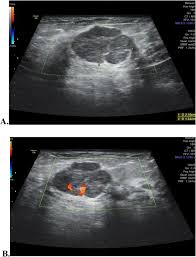

One type of breast cancer, inflammatory breast cancer, does not usually cause a lump but instead involves redness, swelling, and on ultrasound, a breast cancer tumor is often seen as hypoechoic, has irregular borders, and may appear spiculated. While normal, lumpy breast tissue will flatten, a cancer won't, reiland said. Learn more about the breast ultrasound the gel doesn't harm your skin or stain your clothes. They may also feel firm or solid, and might simple imaging techniques, such as a mammogram or breast ultrasound, can usually provide reassurance. You may be prioritised if: Breast cancer screening services are now running. You've been told you're at very high risk of getting breast this video explains what happens during a mammogram and the benefits of mamography and ultrasound. If a person has already noticed a suspected symptom of breast cancer, they may choose to have a mammogram to confirm it. In the table the differences in ultrasound appearances are listed. Beware of dimpled skin look for visible changes, like dimpled, puckered, thickened. This is because it may miss. Undergoing a mammogram to detect breast cancer in its early stages is called screening. Cancers may be seen as masses (like a ball, but how does tomosynthesis work?

Any area that does not look like normal tissue is a possible cause for concern. In the table the differences in ultrasound appearances are listed. Needing a breast biopsy doesn't necessarily mean you have cancer. Ultrasound imaging is one of the most frequently used diagnosis tools to detect and classify abnormalities of the breast. Breast ultrasound is an imaging test that uses sound waves to look at the inside of your breasts.